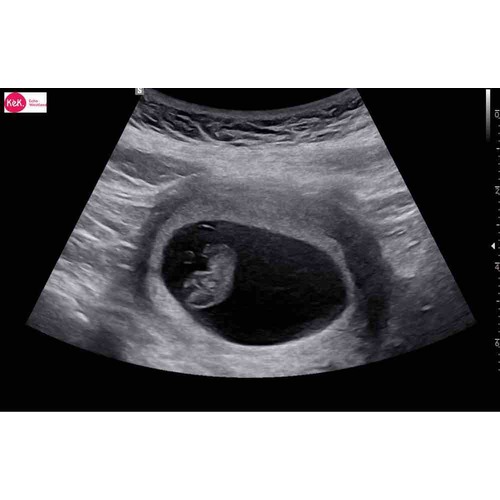

Bij mij was mijn vruchtzakje ook helemaal niet mooi rond. De gynaecoloog heeft hier ook nooit iets van gezegd. Intussen is ze al bijna 5 maandjes oud🥰

Als ik naar al mij 4 keer de zwangerschappen en echo's heb gekeken rond de 6 weken was het bij mij ook allemaal hobbelig en niet mooi rond. 1 van alle is esn miskraam geworden maar dat konden ze niet zien aan de vorm ik heb het ook echt nog nooit gehoord... de volgende echo's werden ze al wat mooier rond... maar hun hebben ervoor gestudeerd... wanneer mag je terug?

Hoi allen, hoe is het uiteindelijk bij jullie allemaal verlopen? Wij hadden gister onze eerste echo (ongeveer 6.3 wk) en onze Vk was ook wat voorzichtig met goed nieuws brengen door de vorm van de vruchtzak. Echter wel een hartslag; langzaam maar dit hoeft nog niets te betekenen met dit termijn.

Ik heb tijdens bloedverlies twee echo's gehad met een kloppend hartje. Veel stolsels ook om de vruchtzak heen in mijn baarmoeder.

Vier dagen later op de echo geen kloppend hartje meer en de vk zei toen nog dat de vruchtzak er ook niet mooi rond meer uit zag. Dus bij mij was dat helaas geen goed teken.